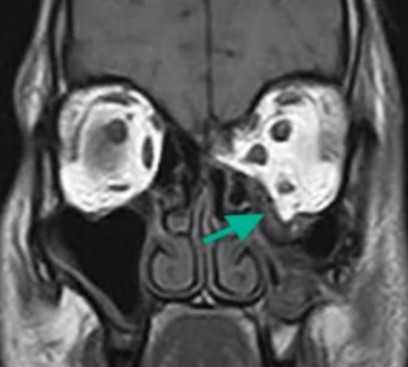

Метод применяют для диагностики новообразований, при подозрении на инфекционно-воспалительные процессы, гнойное расплавление тканей. По снимкам МРТ планируют лечебные хирургические вмешательства, пластические операции, вспомогательные процедуры при диагностике различных опухолей (менингиома, остеома, остеобластома и пр.). Основные данные о состоянии костей получают при КТ.

Взрывной перелом орбиты на МРТ (изменения указаны стрелкой)